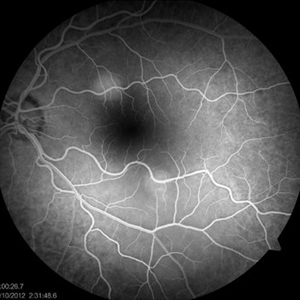

Multifocal Central Serous Chorioretinopathy OS

Aug 24 2012 by John S. King, MD

26 sec

Photographer: Kristin Konecki, OcuSight Eye Care Center, Rochester, NY

Condition/keywords: central serous chorioretinopathy (CSCR), multifocal central serous chorioretinopathy (CSCR)

Multifocal Central Serous Chorioretinopathy

14 min Autoimmune Hepatitis; slowly tapering prednisone; lesions resolved with lfPDT, but could not download movie of the OCTs because file too large.